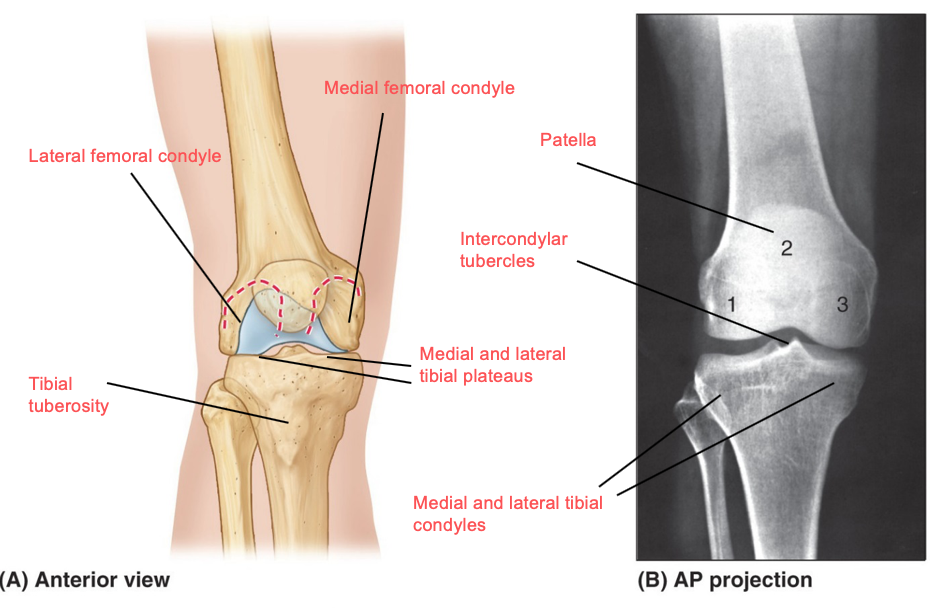

What components involved in stability are represented by the red, green and blue lines?

red:

intra-articular ligaments (inside the joint)

green:

extra-articular ligaments (outside the joint)

blue:

surrounding muscles